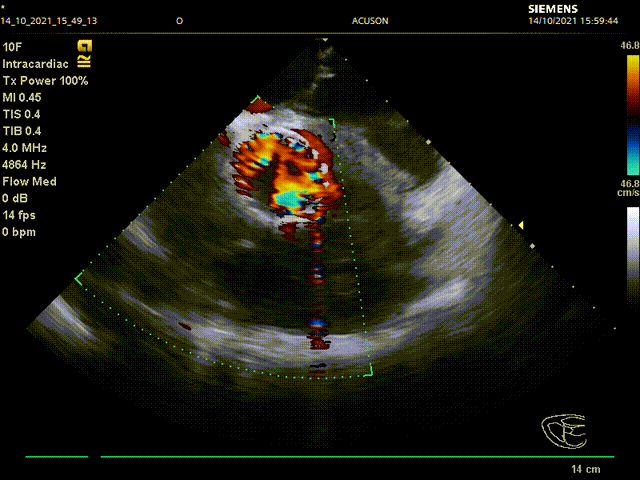

ICE辅助下TAVR手术

VenusAplus32释放

术后患者跨瓣压差由48下降为2,无瓣周漏,患者症状改善,一周后出院。